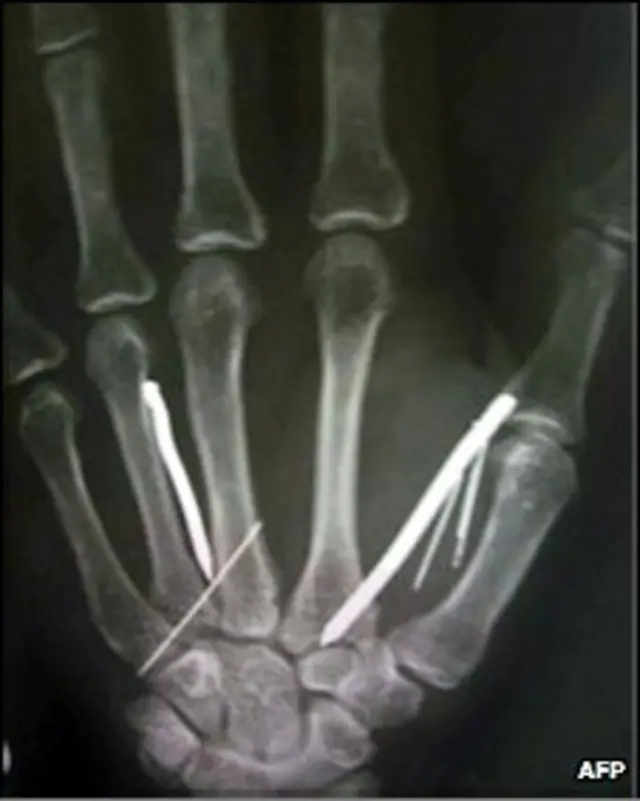

پزشکان در ماه اوت گذشته سیزده سوزن و پنج میخ را از بدن این خدمتکار بیرون کشیدند. او گفته که کارفرمای او با استفاده از چکش، میخ و سوزن به بدنش فرو می کرده است.

عکسبرداری با اشعه ایکس از بدن او نشان داد که ۲۴ سوزن و میخ در پاها و دست های این زن فرو رفته است. یکی از مسئولان بیمارستان گفت که طول هر یک از این میخ ها پنج سانتی متر بود.

خانم آریاروثی که سه فرزند هم دارد، سه ساعت تحت عمل جراحی قرار گرفت تا پزشکان بتوانند بیشتر میخ ها و سوزن ها را از بدن او خارج کنند. برای بیرون کشیدن سوزن های باقیمانده در بدنش هم باید عمل جراحی دیگری صورت گیرد.